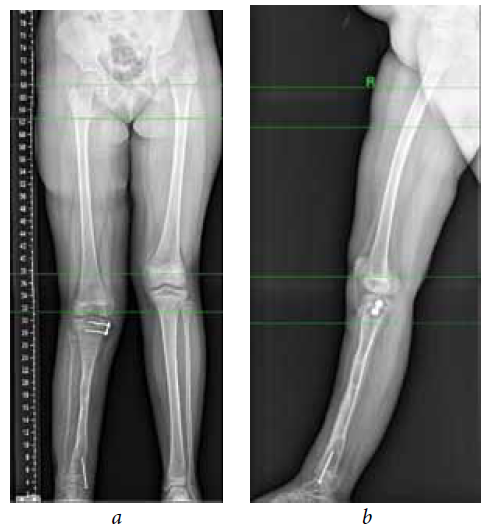

The second stage of treatment was the recommended correction of the resulting multiplane deformities of the affected lower extremity (mMPTA was 94°, mLDTA was 71°, aPPTA was 90°, and aADTA was 59°, shortening the affected lower limb by 8.0 cm). For lengthening and deformity correction of the right lower limb, the patient underwent preoperative planning for deformity correction with the exception of osteotomies in the area of consolidated pseudoarthrosis at the age of 9 years. According to the plan, a two-level osteotomy of the shin bones was performed, as along with lengthening by 5 cm by the Ilizarov method. The deformity was corrected using a repositional unit with Ortho-SUV computer navigation properties. The period of deformity correction was 58 days, and the external fixation period was 247 days. At the end of the fixation period, a recurrence of deformities of the tibial bones was detected with the formation of a deformity apex at the level of the proximal and distal tibial growth zones (mMPTA was 94°, mLDTA was 82°, aPPTA was 86°, and aADTA was 80°) (Fig. 1–4). We applied hemiepiphysiodesis to correct the recurrence of valgus deformity of the tibia. The period of deformity correction was 269 days. The reference angles values of the tibia were within the accepted ranges.

Fig. 4. Roentgenograms of the patient with cCPASB following deformity correction of the bones of the right tibia: а — anterior-posterior view; b — lateral view